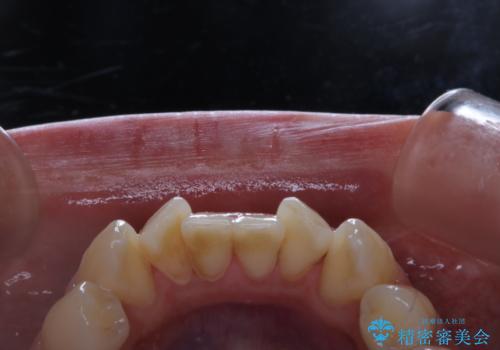

歯周病とは、細菌による感染症です。歯周病菌を取り除くには、歯周ポケットの中を機械的に掃除することです。

歯周病の原因は、歯にべったりと付着するプラーク(細菌の塊)や歯石です。そこから歯周病菌が引き起こす炎症により、歯を支える歯周組織が破壊され、最終的には歯が抜け落ちてしまうという怖い病気です。

もっとも、効果的な治療法がPMTC(歯科医院で専門的な機械や材料を使用してクリーニング)を定期的に行うことです。